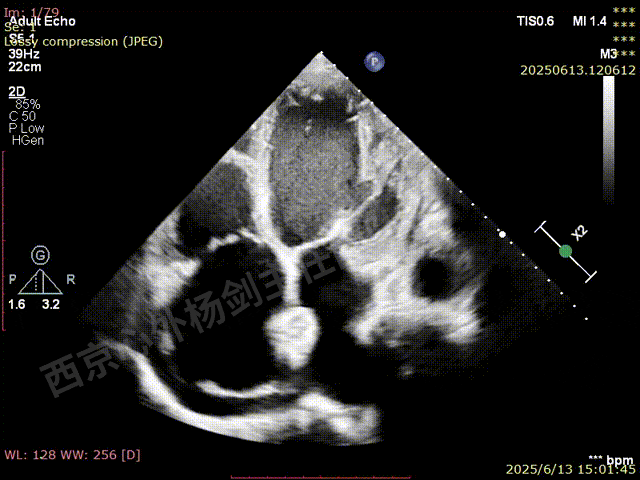

TAVR术后,全心增大,二尖瓣反流重度,三尖瓣反流重度。中量心包积液。左室严重增大,标准图像调整困难。主动脉瓣位带支架人工瓣膜瓣叶启闭正常,主动脉瓣位人工瓣上血流速度Vmax 148cm/s,PGmax 9mmHg,Vmean 86cm/s,PGmean 2mmHg, VTI 34.7cm,瓣周反流(轻)。估测肺动脉收缩压约49mmHg;左室收缩功能明显减低。LVEF:23%,EDV:364ml,ESV:221ml。

彩色血流示:二尖瓣反流缩流颈彩宽6.6mm,面积17cm²,容积30ml;二尖瓣瓣口面积6.6cm²,瓣环内径:左右径34mm,前后径34mm。2区瓣叶长度:前叶36mm,后叶20mm,叶环比1.6. 三尖反流面积17.2cm²,容积33ml,Vmax 291cm/s,PGmax 34mmHg。

术前3D数字模型